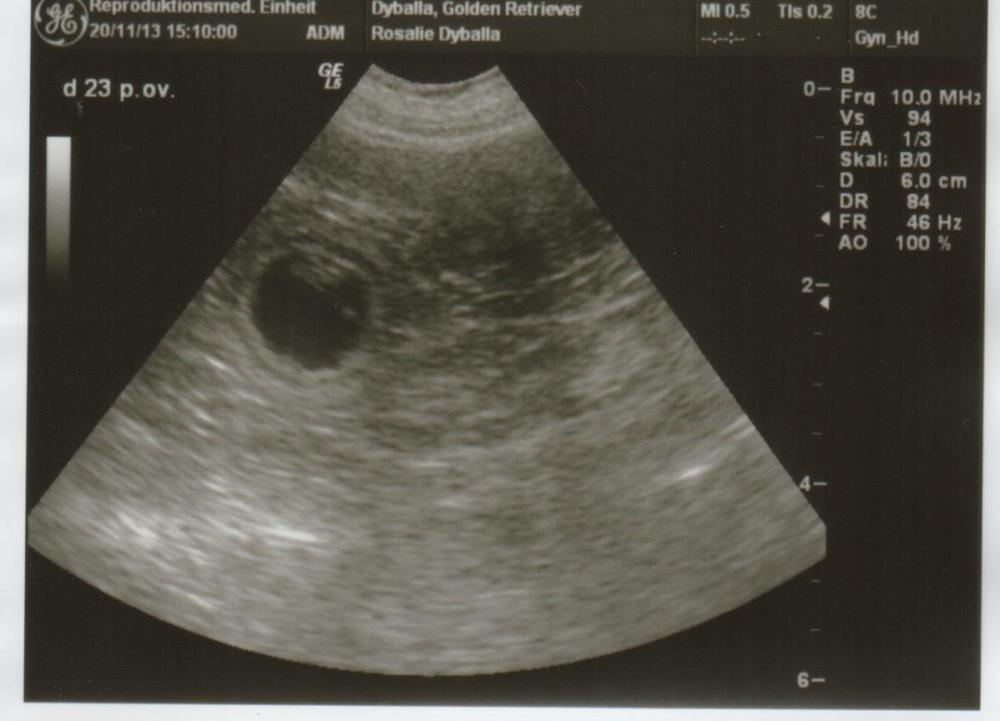

Sie schläft viel aber sonst geht es ihr super gut. Heute am 23.Tag nach Ovulation waren wir zum Ultraschall mit Rosalie und wir haben uns nicht getäuscht.

Rosie ist trächtig. Frau Dr. Urhausen von der Tierärztlichen Hochschule Hannover (Reproduktion) hat viele Fruchtanlagen gesehen.